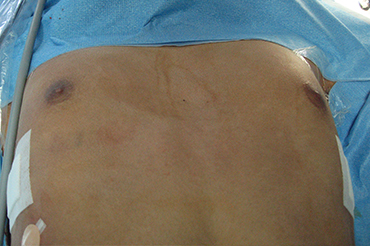

Pectus Excavatum

Adolescentes